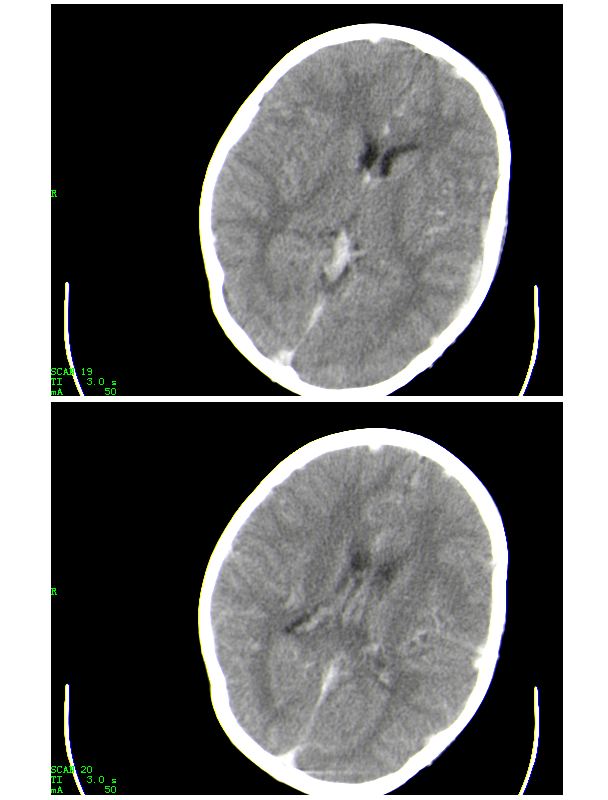

男,13岁,头部外伤后头痛、呕吐三小时就诊,查体,见小孩精神状态尚可,面部,嘴唇青紫明显,后作心脏彩超证实为“发四”,有复查片,大家先看看首诊片,考虑什么

感谢大家的关注,本例我们最后诊断为高血红蛋白症所致的脑血管改变,患者血红蛋白258g/l

下面是第二天的复查和受伤后第五天的复查,左侧硬膜下血肿有所吸收,脑内条状高密度无改变